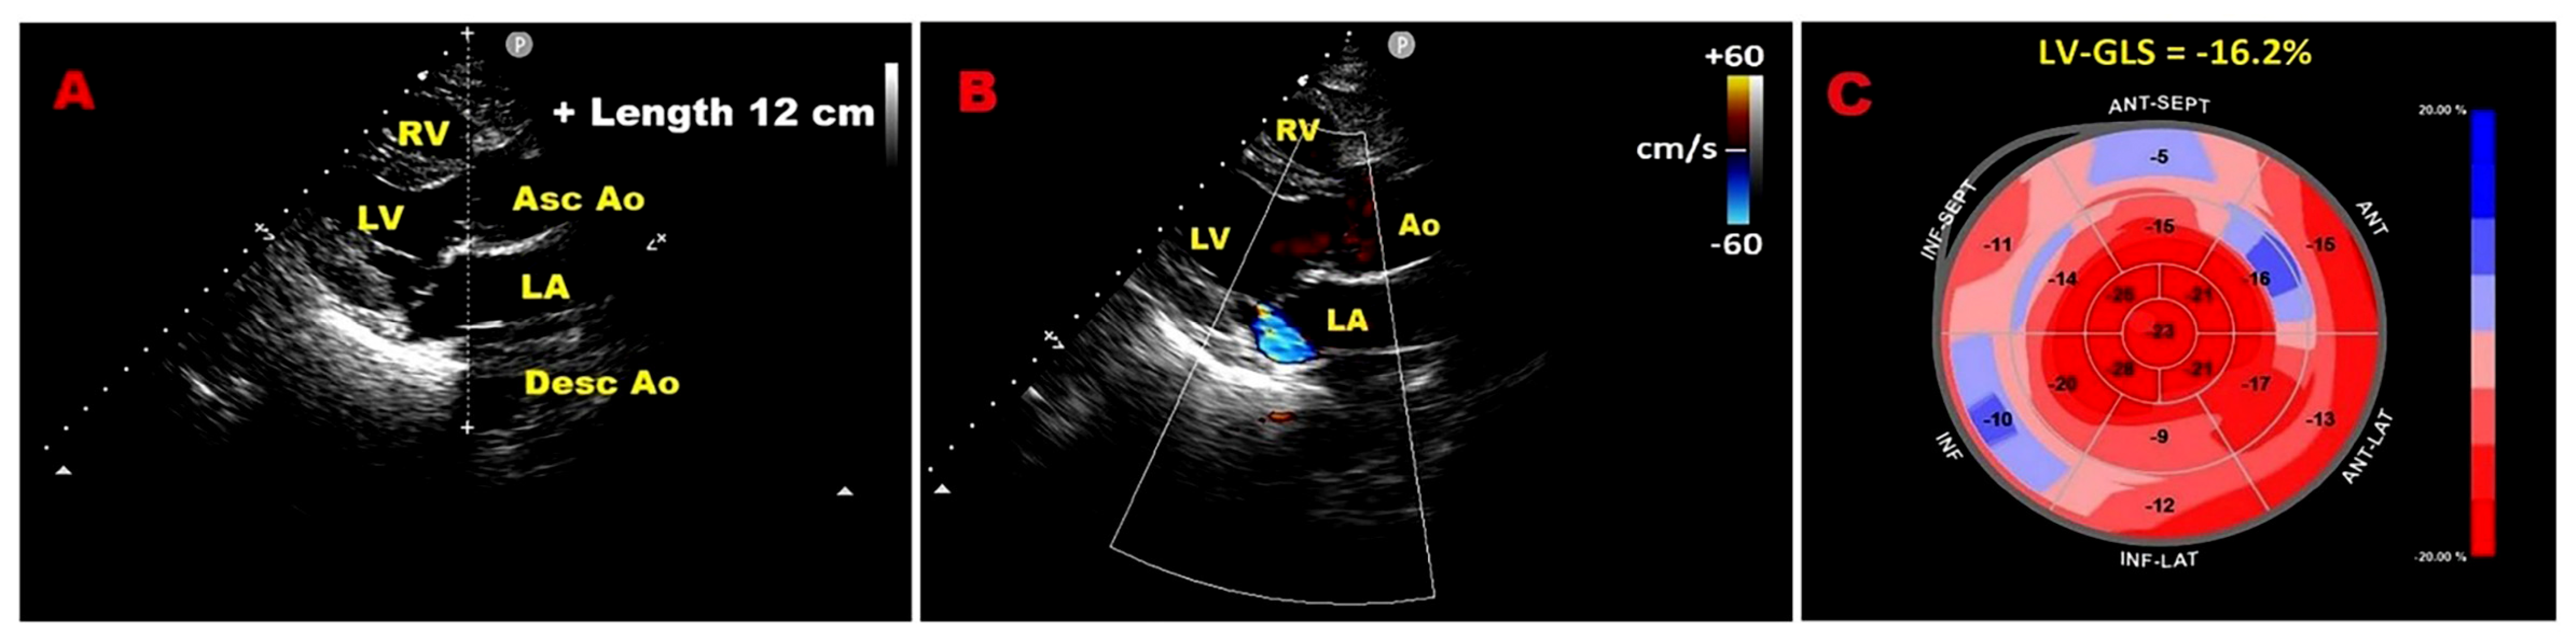

3.7. Pulmonary Hypertension

3.10. Functional Tricuspid Regurgitation

9.2. Relationship Between Chest Wall Conformation and MAD Distance in PMR with MVP

9.4. Influence of Chest Wall Conformation on ESE Results